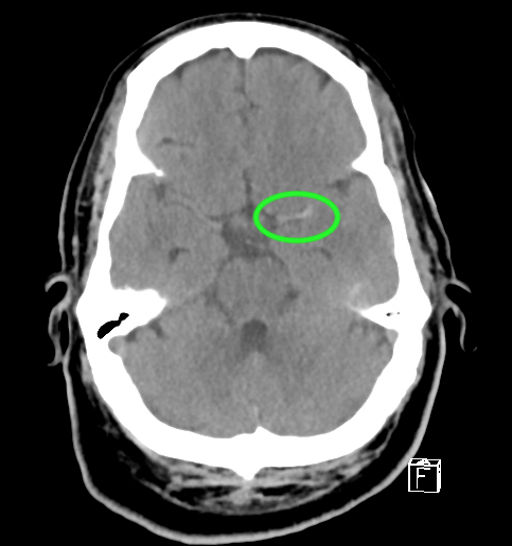

Figure 13. Notice asymmetry, loss of gray/white differentiation, loss of the insular ribbon, and hypodensity in the posterior right MCA distribution. Image courtesy of the Baylor Scott and White Memorial Hospital–Temple, Texas.

Figure 14. MCA sign. Please note the asymmetry, loss of gray and white differentiation, loss of insular ribbon, and a hyperdense MCA sign in the left middle cerebral artery, consistent with clot (green circle). Image courtesy of the Baylor Scott and White Memorial Hospital–Temple, Texas